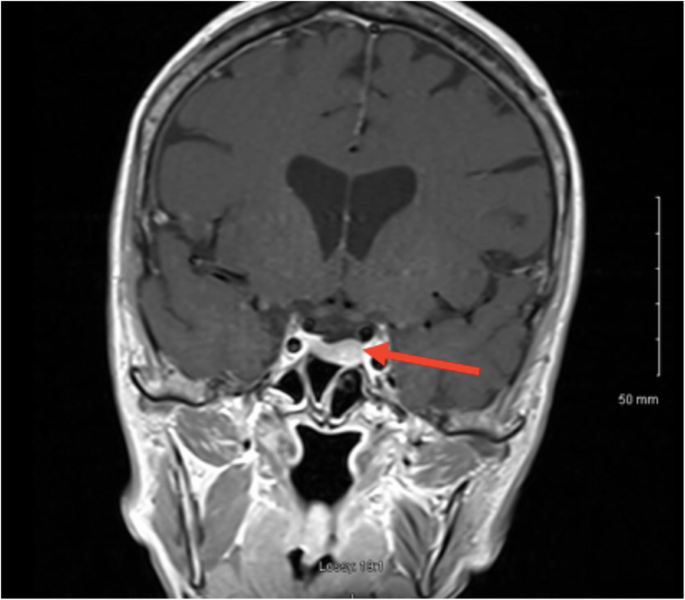

A pituitary MRI scan showed asymmetric enlargement of the gland, raising the possibility of a left-sided pituitary microadenoma (Fig. 2). An 11C-methionine PET/CT scan was performed and coregistered with a volumetric [fast spoiled gradient recall (FSPGR) MRI scan (Met-PET-MRICR)]. This demonstrated focal increased tracer uptake at the site of the suspected microadenoma (Figs. 3 and 4). Her biochemical and radiological findings were therefore consistent with the diagnosis of a TSH-secreting pituitary adenoma. The slightly raised IGF-1 and borderline suppression of GH on OGTT also raised the possibility of GH co-secretion. The patient was tried on a somatostatin analogue (SSA) first then a dopamine agonist but did not tolerate either (due to gastrointestinal side-effects). She declined pituitary surgery. She is currently managed with a beta-adrenergic blocker and is clinically euthyroid.